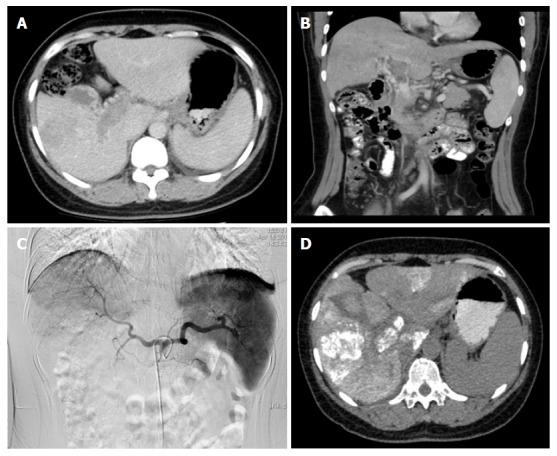

Transarterial embolization and low-dose continuous hepatic arterial infusion chemotherapy with oxaliplatin and raltitrexed for hepatocellular carcinoma with major portal vein tumor thrombus.

Eighty-six patients with MPVTT accepted routine embolization. The catheter was kept in the hepatic artery and oxaliplatin (50 mg in 250 mL of glucose) was infused by pump for 4 h, followed by raltitrexed (2 mg in 100 mL of 0.9% saline) infusion by pump for the next 1 h. The efficacy and safety were evaluated after the transarterial chemoembolization (TACE).

Full or partial embolization was achieved in 86 cases, where all the cases received low dose continuous hepatic arterial infusion chemotherapy. Complete responses (CRs), partial responses (PRs), stable disease (SD), and disease progression (PD) for intrahepatic disease were observed in 0, 45, 20, and 21 patients, respectively. The 1-, 2-and 3-year overall survival rates of the 86 patients were 40.7%, 22.1%, and 8.1% respectively, and the median survival time was 8.7 mo. Complication was limited.